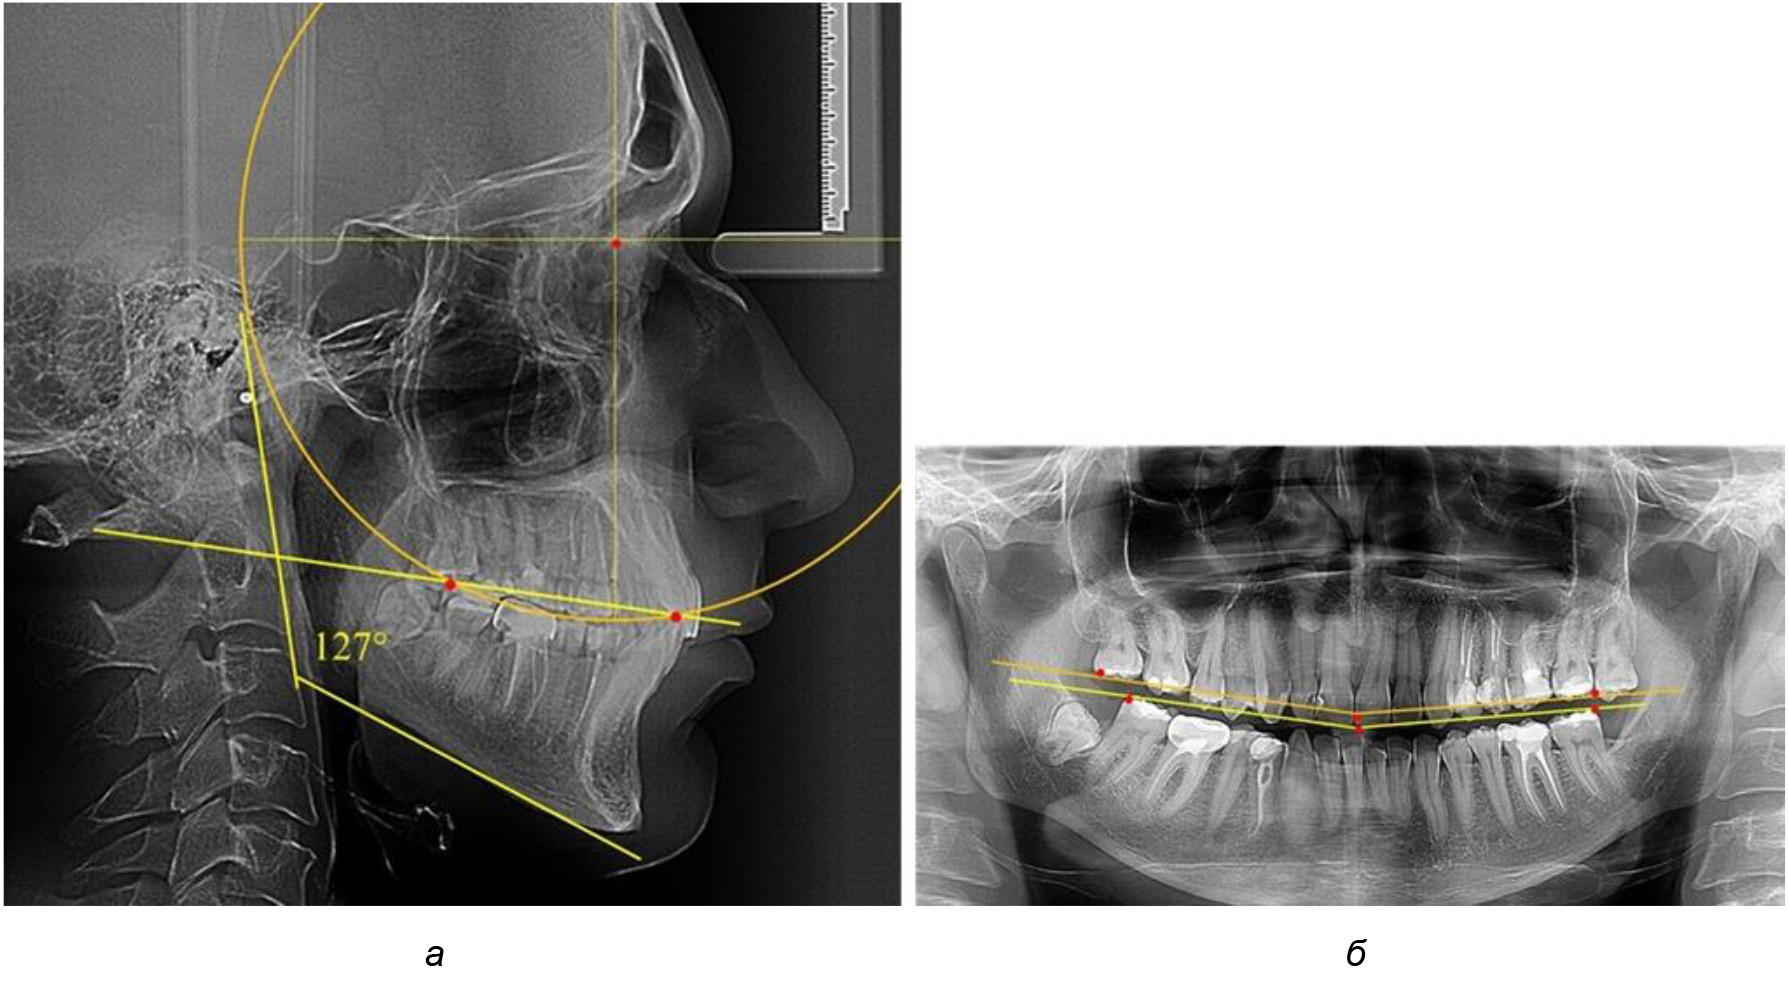

У людей с аномалиями окклюзии по сагиттали в 1-й подгруппе обследовано 9 человек. Обращает на себя внимание увеличение глубины кривой Spee, что нами расценивалось, как патологическая форма кривой линии окклюзии.

Глубина кривой Spee в среднем по 2-й подгруппе составила (5,69 ± 1,57) мм, что было достоверно больше, чем у людей с физиологической окклюзией (р ˂ 0,05). Достоверных различий с показателями, полученными при анализе ТРГ и ОПТГ, нами не отмечено (р ˃ 0,05). Отношение радиуса окружности к сагиттальному размеру окклюзионной линии в среднем по подгруппе составляло 1,372 ± 0,042 и не соответствовало числу Фибоначчи, что может быть использовано в качестве диагностического критерия определения патологической формы кривой Spee. После лечения пациентов техникой «прямой» дуги было отмечено незначительное увеличение сагиттального размера окклюзионной лини в среднем на (2,12 ± 0,77) мм. Однако окклюзионная линия практически касалась окклюзионного контура всех жевательных зубов, и отмечалось практически полное отсутствие кривой Spee.

Таким образом, проведенное лечение техникой «прямой» дуги способствует нормализации окклюзионного равновесия и торку передних зубов, однако не соответствует оптимальному окклюзионному статусу, характеризующему физиологическую окклюзию. При этом величина нижнечелюстного угла оставалась на прежнем уровне (рис. 5).

Рис. 5. Особенности ТРГ при патологической кривой Spee до лечения (а) и после лечения (б) техникой «прямой» дуги